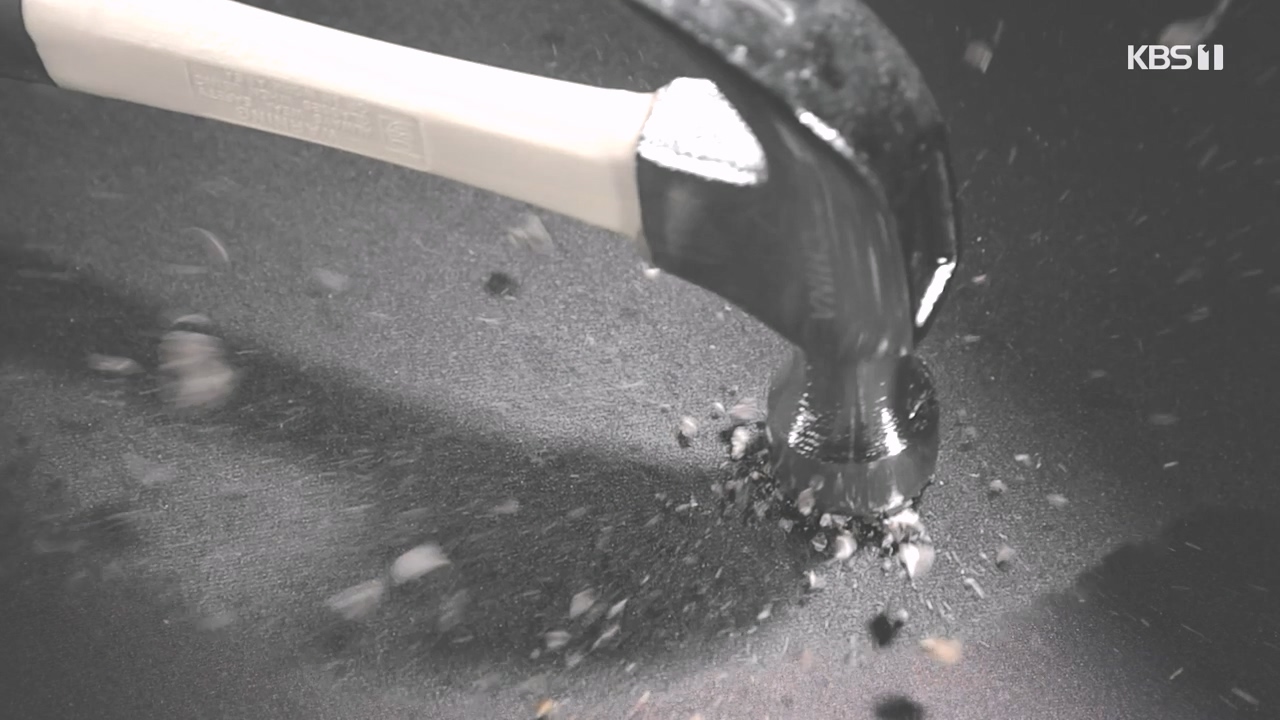

예고 없이 나타난 극심한 복통, 담석증

다양한 합병증을 유발하는 몸속 시한폭탄, 담석증

내 몸의 치명적인 돌 담석증